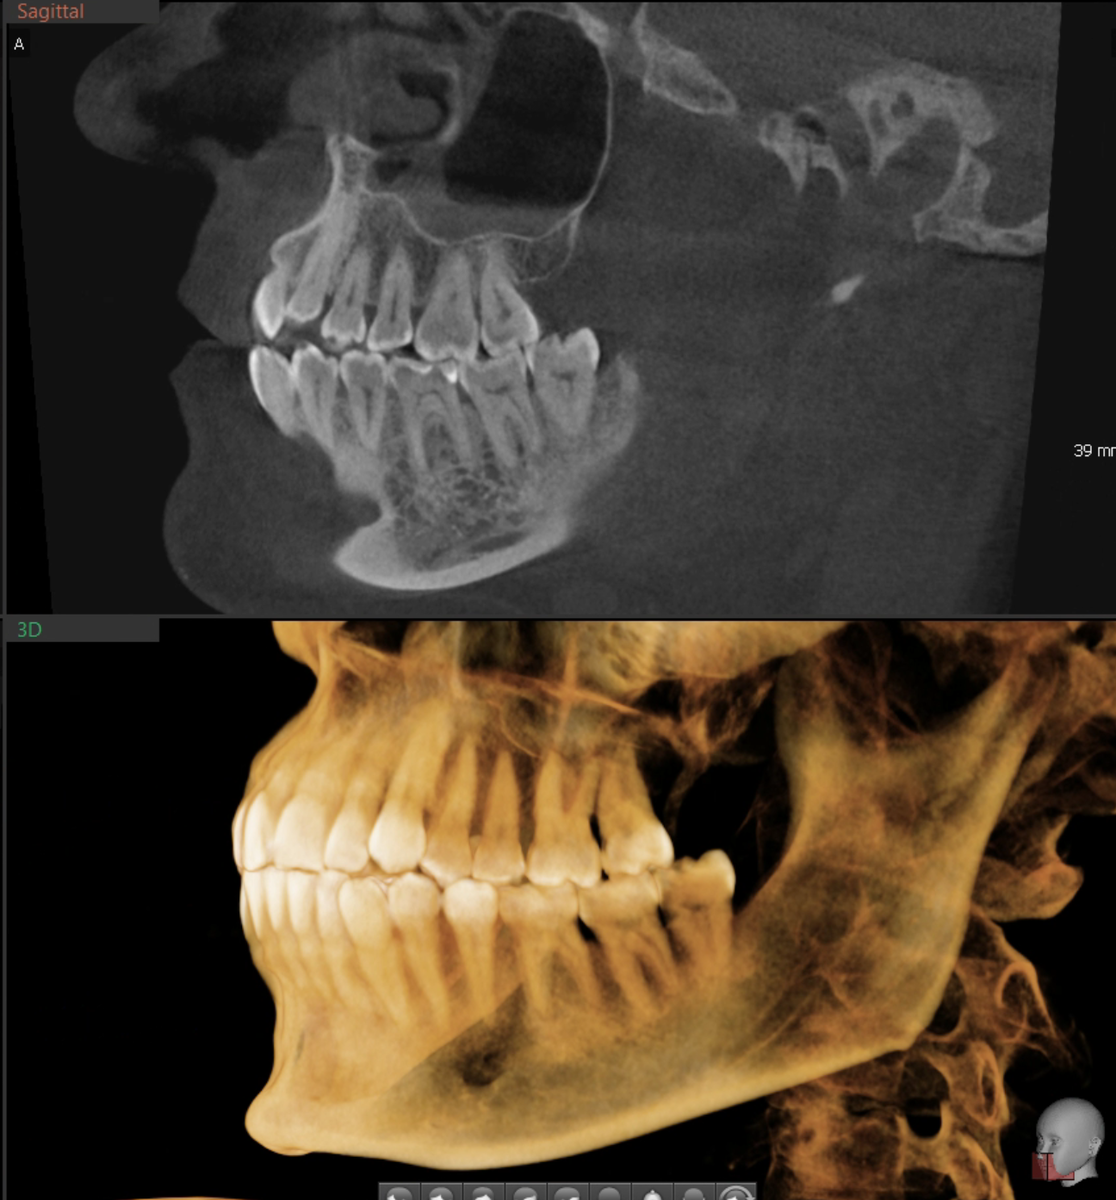

Вернёмся к нашей пациентке. Если вы тему усвоили, то увидите, что воспаления нет в её случае, кость цела.

Значит, рецессии перегрузочные.

Прикус интересный - скелетный третий класс, это когда нижняя челюсть выдвинута вперёд. Плюс перекрёстное смыкание в боковом отделе - нижние зубы перекрывали верхние, что создавало вынужденное положение челюсти.

Передаю пациентку в руки ортодонта Снитковой Ксении Владимировны. С начала 2025 года идёт коррекция прикуса на элайнерах.